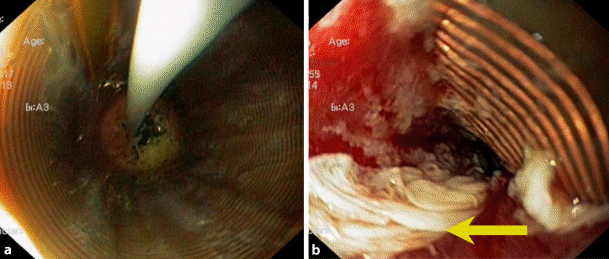

Fig. 3

Antegrade endoscopic view during RFA in the distal esophagus, using the catheter-mounted balloon (RFA 360). a View through the treatment balloon during the delivery of the radiofrequency energy to the tissue, as described in the text. b Image after RFA treatment with the balloon deflated. The yellow arrow indicates the ablated mucosal tissue. Note the red surface of the submucosa indicating adequate ablation

Endoscopic BE treatment

Endoscopic therapies for the elimination of BE include endoscopic mucosal and submucosal resection for the removal of nodules and tumors within the CLE [3]. RFA represents a modern endoscopic therapy for the removal of endoscopically flat visible CLE containing BE, LGD, HGD, and early cancer ([2, 3], Figs. 2 and 3). The radiofrequency energy is applied to the CLE under endoscopic vision from self-sized balloon catheter-mounted electrodes (RFA 360; Fig. 3), an endoscope tip (RFA 90, 60), or working channel-mounted electrodes (“eagle” device; [2, 3]).